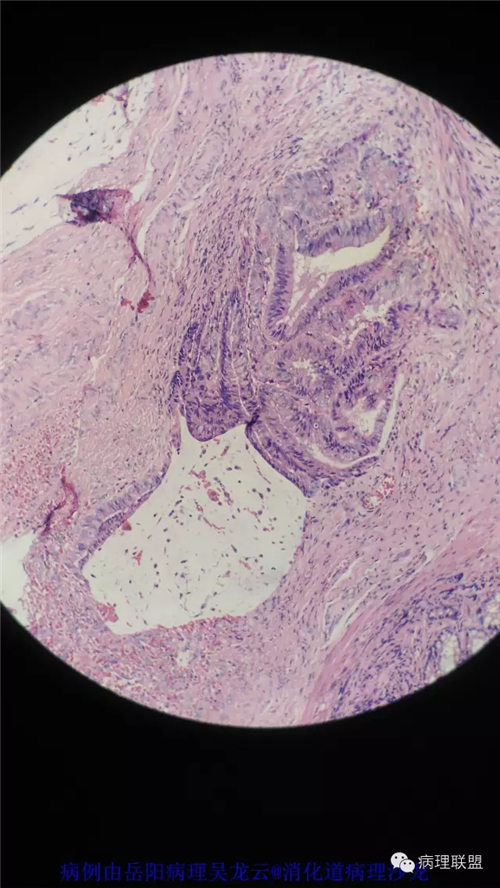

病例2

病史

女性,60岁,结肠腺瘤活检。有一灶腺体突破粘膜肌,腺体无明显异形。

(注:病例由岳阳病理吴龙云提供 致谢!)